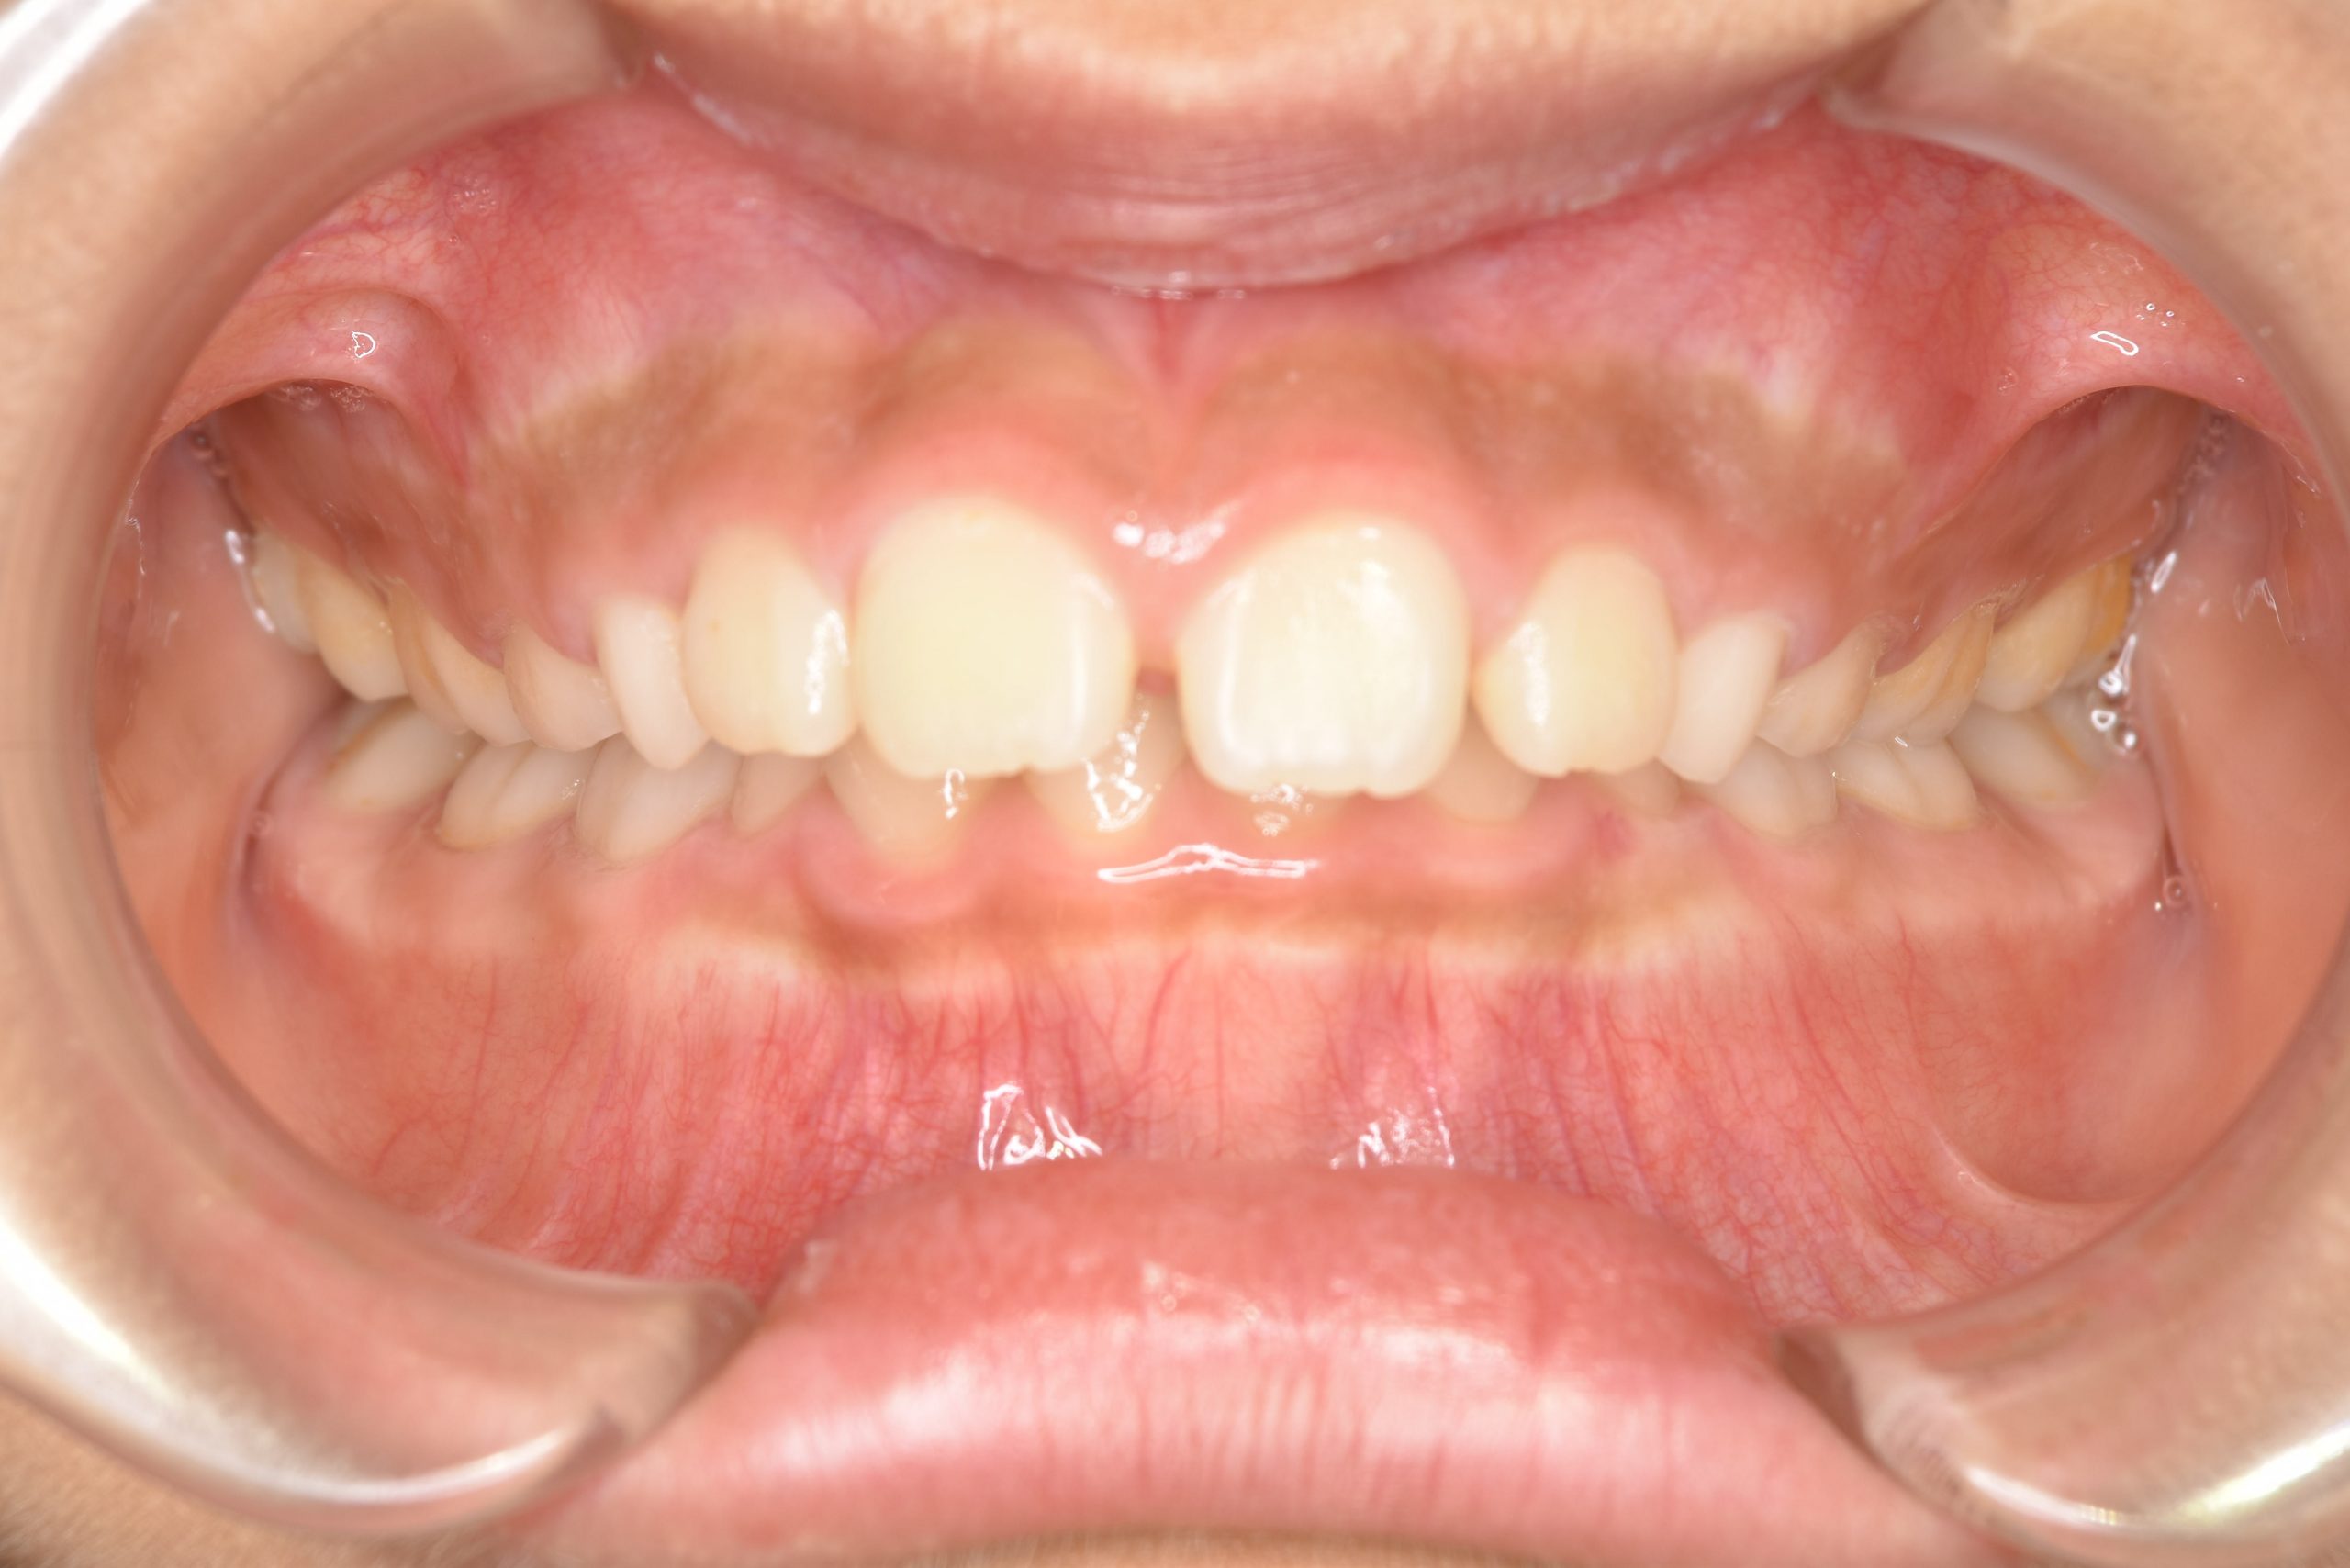

子どもの矯正治療|症例_547 Case

ビフォー

主訴 上下の歯が接触しない

施術内容 上顎急速拡大装置と下顎リンガルアーチを用いて上下顎骨を拡大した。

その後マウスピース型矯正装置で歯牙を配列し良好な咬合を獲得した。

治癒期間 2年10か月